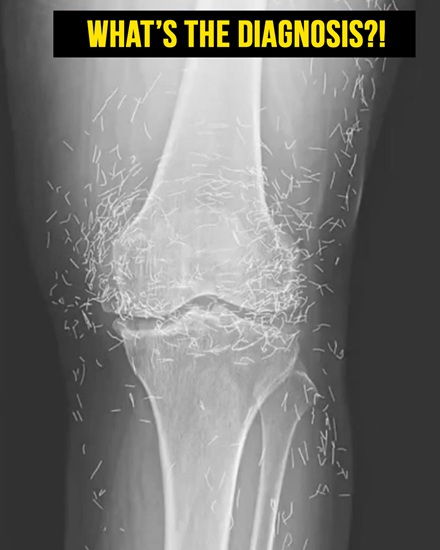

The woman’s X-rays revealed multiple tiny gold needles embedded deep within her knees. Radiologists noted the unusual density and placement, highlighting both the therapeutic intent and the potential risks of retained acupuncture objects.

Embedded needles can also interfere with medical imaging. X-rays may be obscured, complicating the evaluation of bones and joints. In some cases, retained objects require additional imaging considerations or modified diagnostic approaches.

MRI procedures are particularly risky for patients with metallic needles. Magnetic forces can cause metal to shift inside the body, potentially damaging tissues or nearby arteries, making careful assessment critical before any imaging.